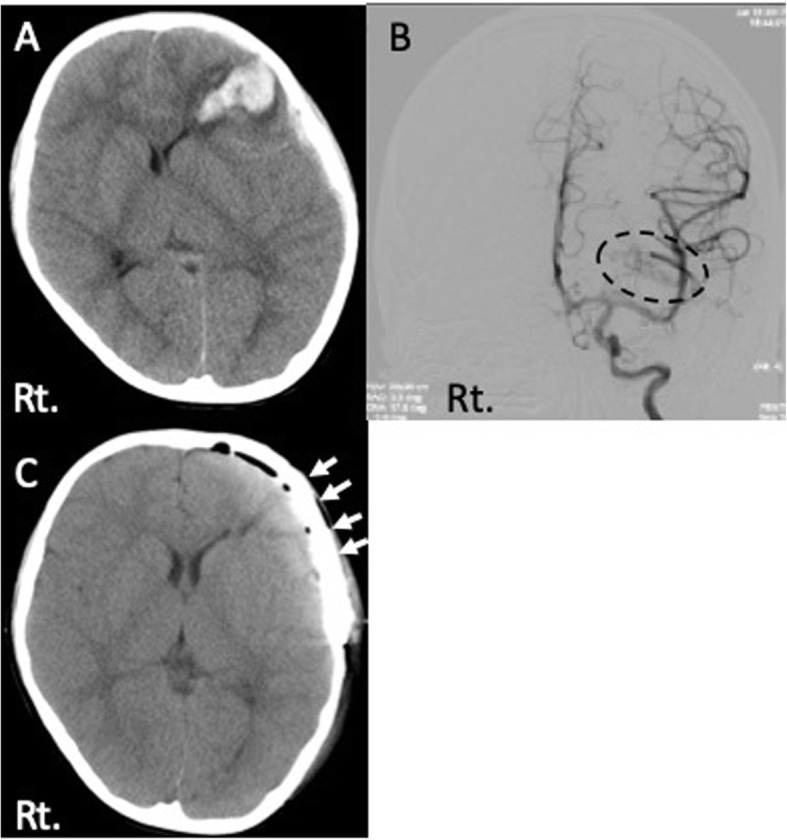

A 5-year and 11-month-old boy presented with left frontal subcortical hematoma due to ruptured AVM and underwent the removal of AVM with the decompressive craniectomy [Fig. 1a, b]. Four months after the initial surgery, cranioplasty was performed using microporous hydroxyapatite (APACERAM®). We used two bioresorbable plates and eight screws (Lactosorb®) at the frontal region and one titanium plate at the temporal region to fix the artificial bone flap [Fig. 1c]. He was discharged without any neurological deficit after initial treatment.

Fig. 1.

Radiological examinations at first treatment. a Head CT showed left frontal subcortical hematoma. b Cerebral angiography of the left internal carotid artery showed AVM adjacent to the hematoma (dotted ring). c CT image after cranioplasty